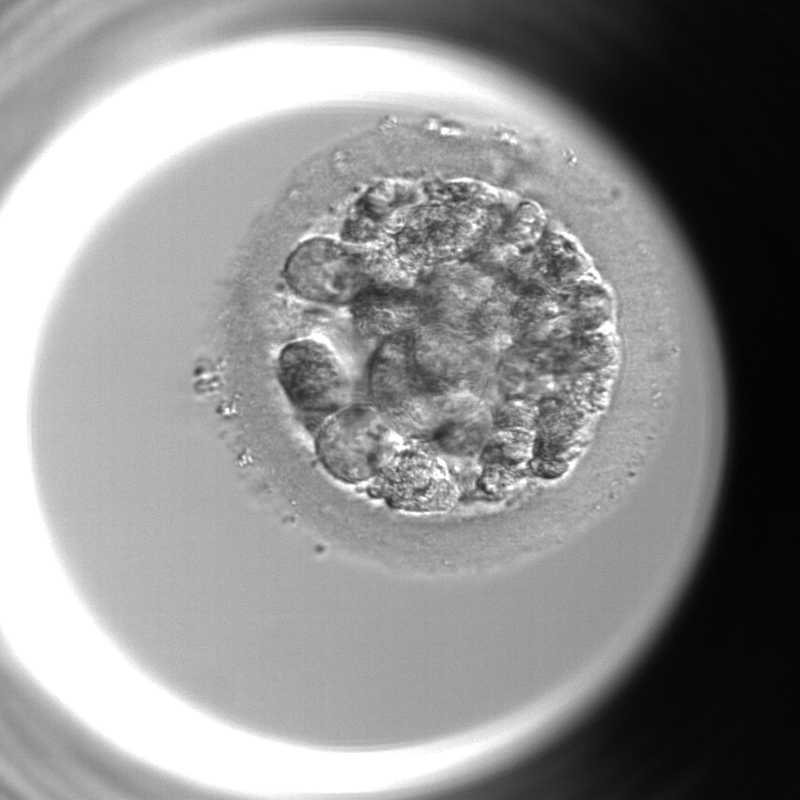

胚盤胞の特徴

胚盤胞になると、分割胚とは明らかに違い、胚には将来赤ちゃんになる内部細胞塊と将来胎盤になる栄養外胚葉があり、より生命の発生に近づいた構造を見せるようになります。評価はこれらの細胞を胚培養士が見た目での形態観察でおこない判定しています。

胚盤胞の様子

受精後5~6日目

受精後5~6日目の胚盤胞を対象に、胚盤胞がどれだけ成長して膨らんでいるかをみる拡張度ステージ、将来的に胎児となる部分の細胞の数や密度をみる内細胞塊ICM評価、将来的に胎盤となる部分の細胞=栄養外胚葉TEの状態、この3つの要素(数字と2つのアルファベット)で評価判定します。